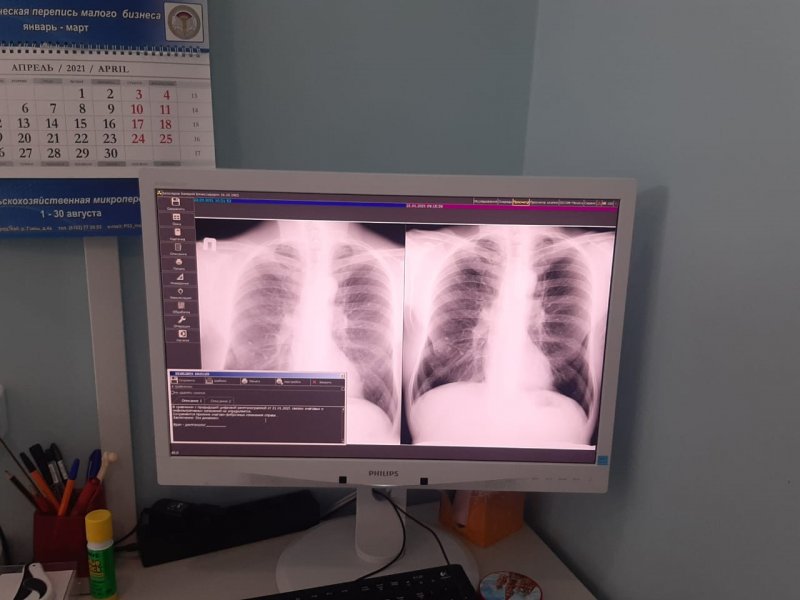

До 26 марта каждый желающий может без направления обратиться в противотуберкулезный диспансер и пройти флюорографическое исследование, спирографию, экспресс-тестирование на ВИЧ-инфекцию, получить консультацию детского или взрослого фтизиатра. Детям могут сделать манту или диаскинтест.

«Пациенты участвуют в этой акции очень активно. Я приехал на работу к 8 утра, и уже было много желающих пройти обследование. Севастопольцы достаточно активно и внимательно относятся к своему здоровью и пользуются возможностью проверить здоровье без записи к специалисту», — рассказал главный врач противотуберкулезного диспансера Андрей Вербицкий.

Противотуберкулезный диспансер работает с 8 до 18 часов. Детей принимают до 14 часов, взрослых и подростков — до конца рабочего дня. С собой необходим только документ, удостоверяющий личность.